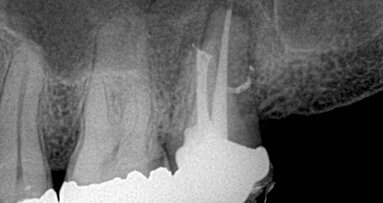

Los Anđeles, USA: Naučnici iz Kalifornije su nedavno radili istraživanje o mogućnostima malenog, ali moćnog saveznika koji može da se upotrebi za prevenciju infekcija nakon tretmana kanala korjena zuba. U kliničkom istraživanju utvrđeno je da nanodijamanti štite dezinfikovane kanale kojrena zuba nakon uklanjanja nerva i zubne pulpe, čime se povećava verovatnoća potpunog oporavka tkiva. Rezultati ovog istraživanja smatraju se veoma značajnim za primenu nanodijamanata kod ljudi.

Istraživači su testirali gutaperke natopljene nanodijamantima kod tri pacijenta kod kojih je rađen endodontski tretman. Testiranje tih gutaperki aplikovanih u kanal korjena zuba pokazali su da su rezistentnije na izvijanje i lomljenje od običnih gutaperki. Kod sva tri pacijenta izlečenje je bilo kompletno, bez bolova (koji inače baš i nisu retka pojava) i infekcije.